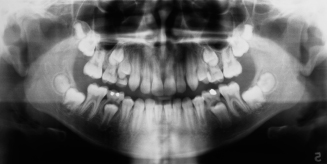

4. How old is the patient with the following X ray?